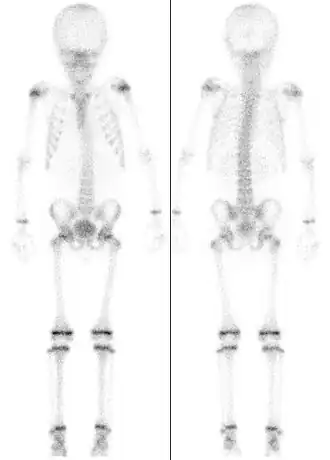

![]() Сцинтиграфия скелета семилетнего ребёнка, демонстрирующая интенсивный обмен в зонах роста. | |